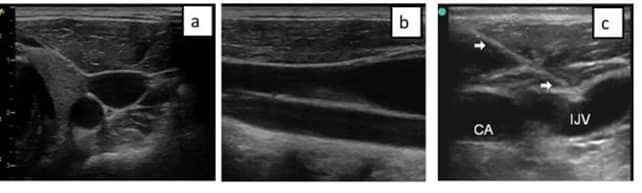

Plano transversal

En el plano transversal, el haz de ultrasonidos corta el vaso perpendicularmente a su eje mayor, dando lugar a una sección circular.

Plano longitudinal

Para obtener el plano longitudinal, debemos realizar una rotación del transductor de 90º, desde el plano transversal, de esta forma visualizaremos la vena en el centro de la pantalla.

- Imposibilidad de visualizar las estructuras adyacentes a no ser que se encuentren en el mismo eje de la vena a nivel superior o inferior.

- Mayor complejidad técnica para la obtención de la imagen adecuada.